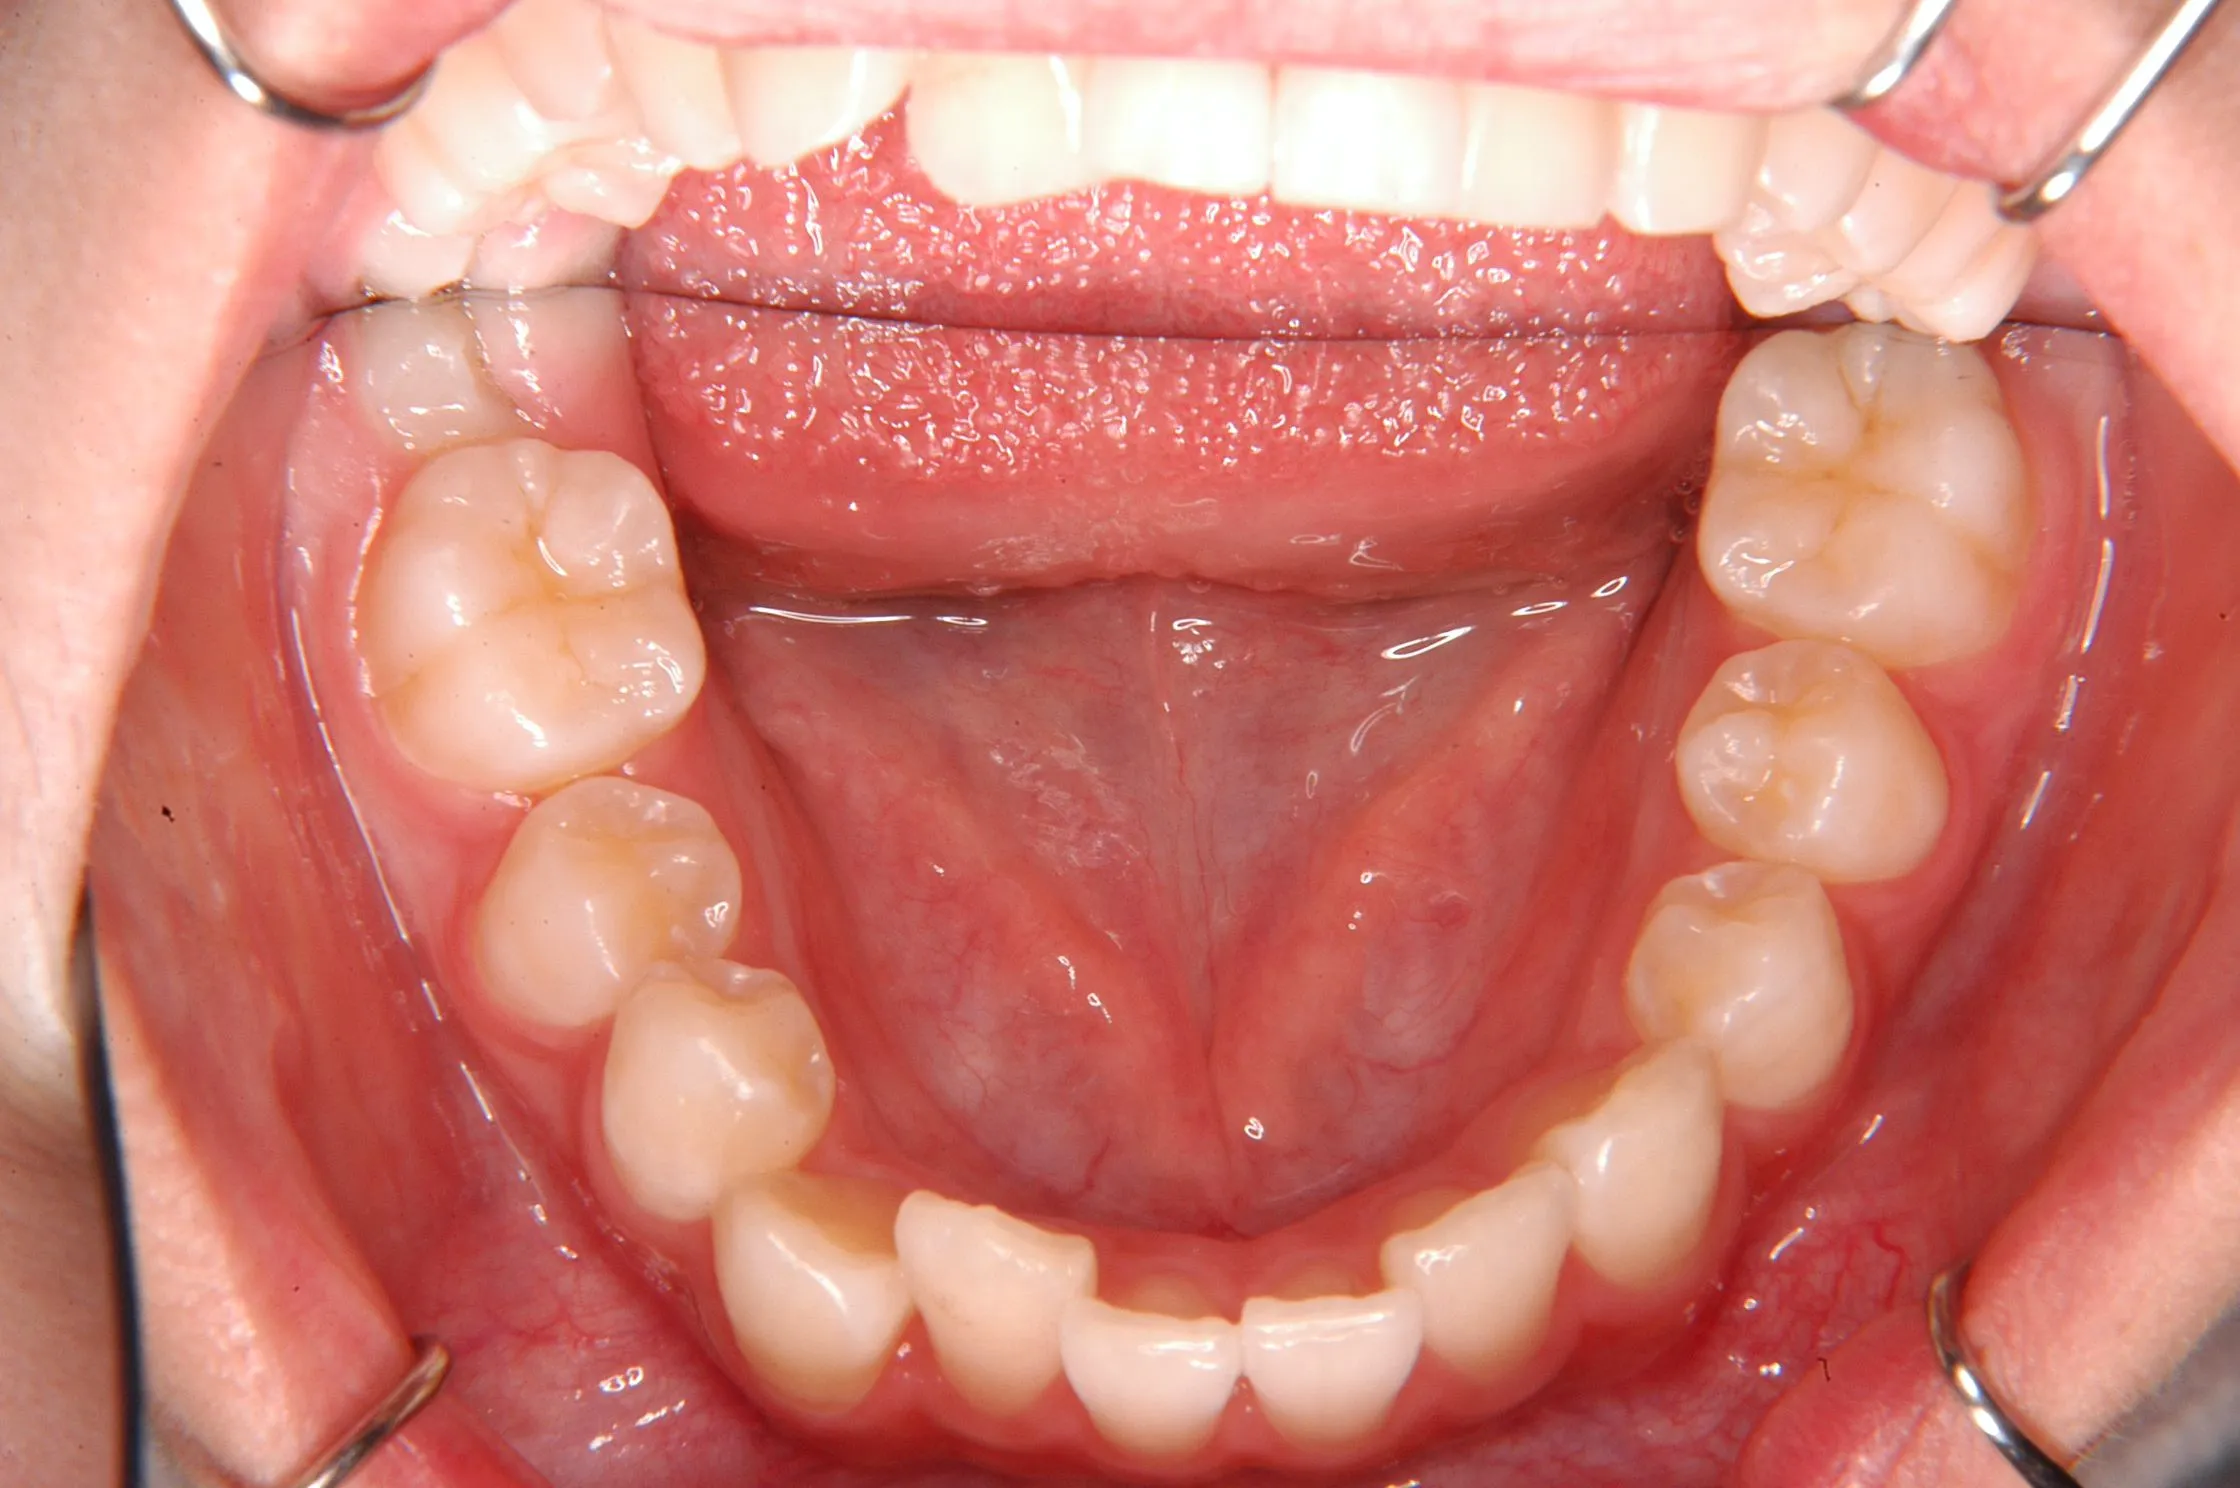

初診時

初診時年齢 小学校6年生 (女性) 主訴 犬歯がずれている・噛み合わない

診断名 叢生・交叉咬合 装置名

右下の犬歯がずれて生え噛み合わせの邪魔をしています。

歯は抜かず、上下マルチブラケット装置を使用し治療いたしました。